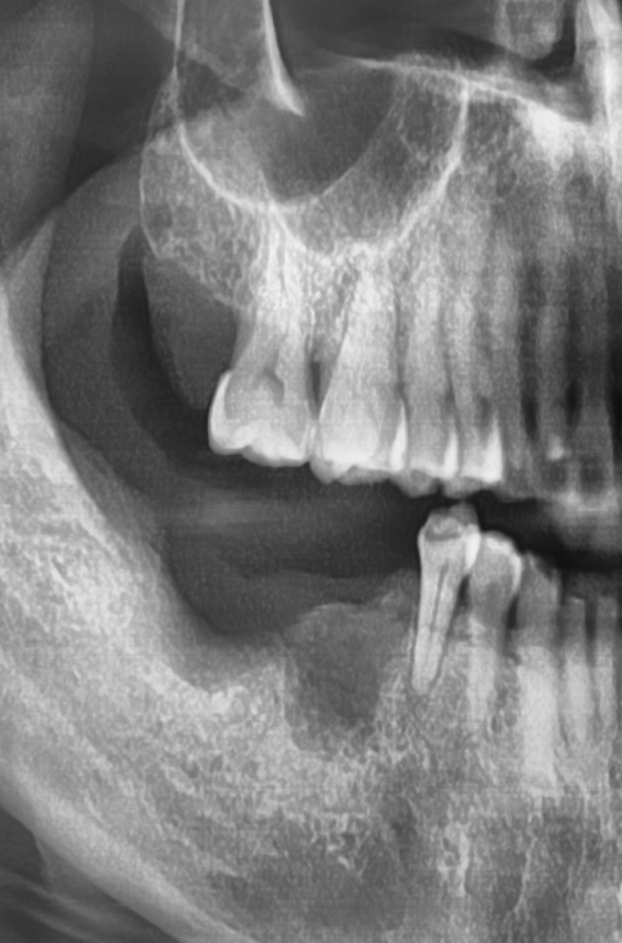

다른치과에서 오래전에 수술한 임플란트가 많이 흔들리고

또한 엑스레이 상에 인프란트 주변 뼈도 많이 녹아있어

묶여있는 임플란트 2개를 제거하였습니다.

두 개 중 하나는 흔들려서 쉽게 제거되었으나 나머지 하나는 상부 뼈가 녹아있음에도

뿌리부분에는 임프란트 픽스쳐가 뼈와 강하게 유착되어 있어 다 갈아내어 임플란트를 제거하였습니다.